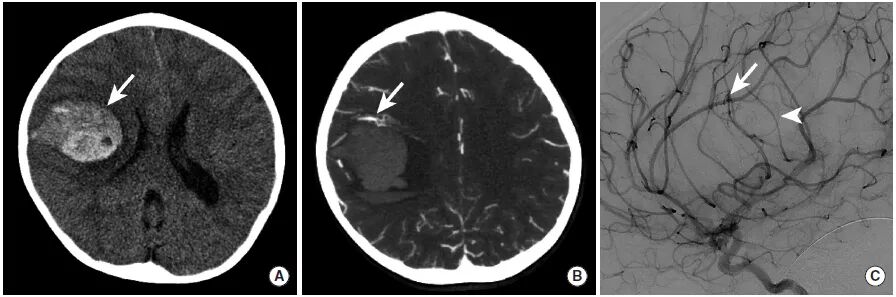

图13

本例为一名儿童患者的影像学检查,由于小

图A:CT平扫显示右额叶高密度影,提示脑实质内出血(长尾箭头)。

图B:CTA的MIP图像显示沿着出血灶的前缘可见的血管缠结(长尾箭头)。

图C:DSA检查确定了动静脉畸形的存在(长尾箭头),并且可见一细小的早期引流皮层静脉影(三角箭头)。